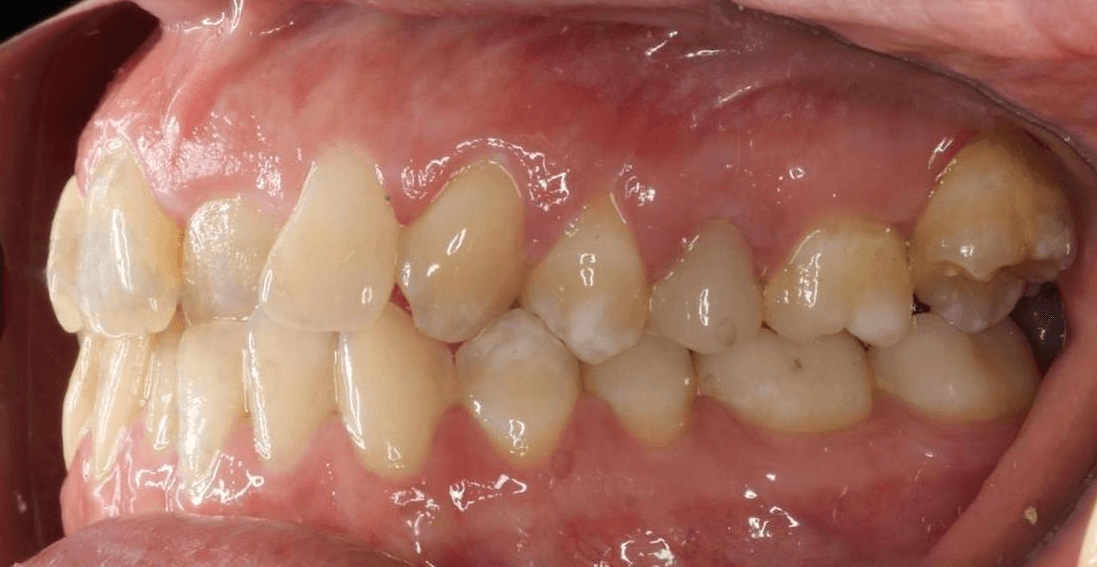

Diganosis: Moderate crowding in both arches, constricted arch forms with anterior and posterior single tooth crossbites, poor smile display

Final results

INTRAORAL